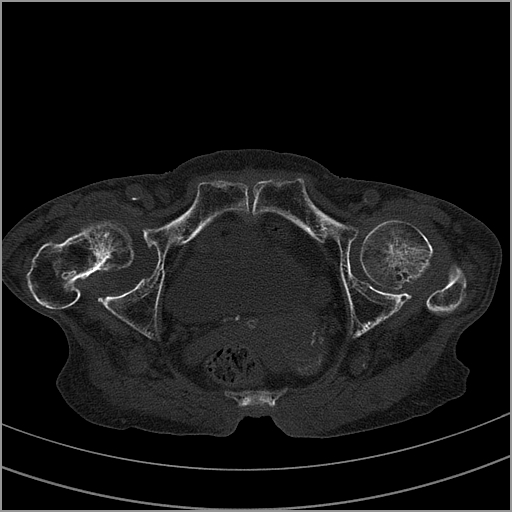

以下是引用老爱克斯新网客在2009-2-3 19:42:00的发言:[br]右侧髋臼及右侧股骨头可见明显骨质破坏,以溶骨性破坏为主,无明显硬化,髋关节间隙变窄,周围软组织明显肿胀,密度不均,脂肪间隙消失。[br] 诊断:右侧髋关节感染性病变,右侧髋关节结核的可能大。[br] 鉴别诊断:1.股骨头缺血坏死,单纯股骨头缺血坏死病例不会累积髋臼骨破坏。2。退行性关节炎,以骨质增生为主,伴有关节面硬化,骨质破坏呈多发小囊状破坏为主,其周围可见硬化环。3.股骨头缺血坏死晚期(第四期)骨质破坏可伴髋关节退行性变,可有骨质增生,但此时骨破坏以股骨头破坏为主,不应该伴有髋臼骨质破坏,因为股骨头的骨破坏是因血运中断,而没有髋臼的血运中断,又没有细菌的感染,怎么能造成髋臼的骨破坏呢。